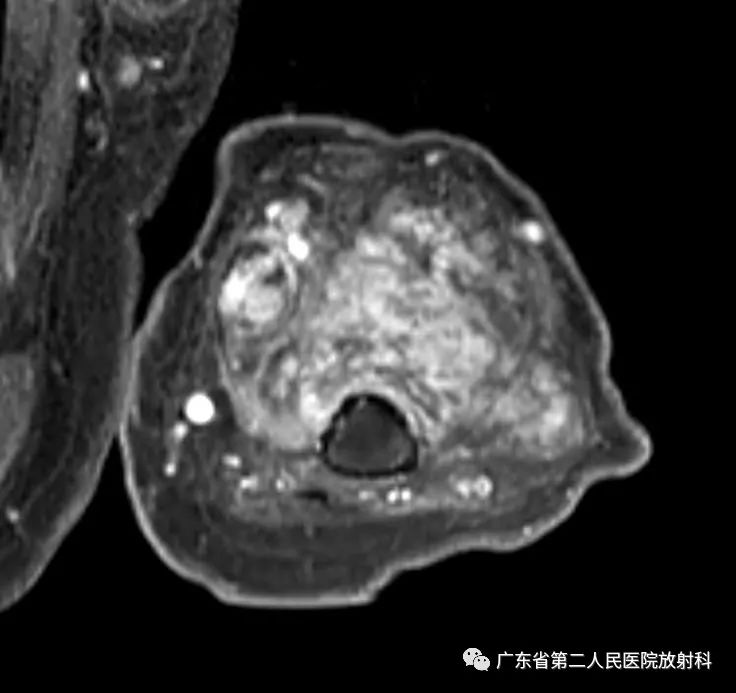

左上肢前壁截肢术后观,左上臂中下段见团块状异常信号,病灶信号明显不均,整体以长T1长T2信号影为主,增强扫描呈明显不均匀强化,末端球形膨大,内见散在少许团絮状短T2长T1且无强化信号。冠状位示病灶整体呈梭形改变,边界欠清,部分包绕肱骨下段,以长T1长T2信号为主,散在少许短T2信号,增强扫描明显不均匀强化,内见散在少许团絮状短T2长T1且无强化信号。肱骨下端边缘欠光整,骨髓未见明确异常信号。